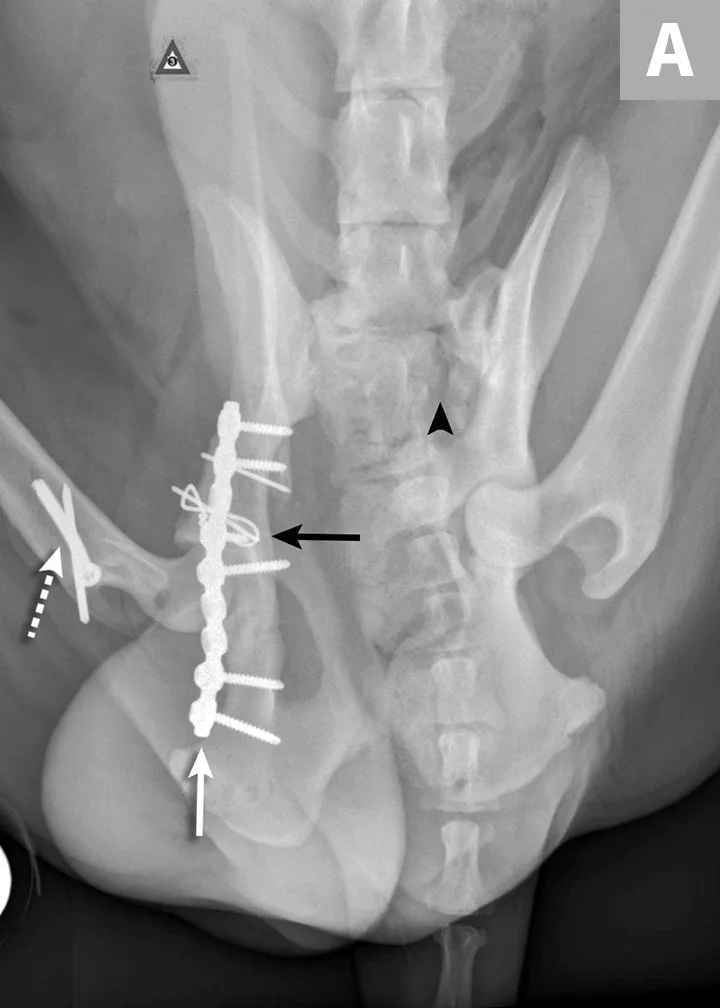

FIGURE 1A

An 11-year-old intact female Welsh corgi with injuries of the weight-bearing axis of the pelvis. Ventrodorsal (A) and lateral (B) projection images show a left sacroiliac luxation with cranial and ventral displacement (black arrow). Pubic fracture with lateral displacement (dashed arrow) and an oblique tibial fracture (white arrows) were additional comorbidities. The tibial fracture was treated surgically with an internal plate fixation, and the pelvic injuries were managed conservatively.